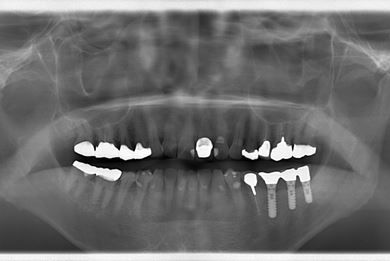

| 性別/年齢 | 男性 / 69歳 | ||||||||||||||||||||||||||||||||

| 主訴 | 1.左上奥歯の詰め物が取れた 2.左上前歯の欠け 3.右下奥歯の欠け | ||||||||||||||||||||||||||||||||

| 治療方針 | セラミック治療にて、審美的回復を行う。 | ||||||||||||||||||||||||||||||||

| 治療内容 | メタルボンドセラミッククラウン1本(メタルボンド用土台1本)、ハイブリッドセラミックインレー1本 | ||||||||||||||||||||||||||||||||

| 総治療費 | 172,410円 | ||||||||||||||||||||||||||||||||

| 治療期間 | 4ヶ月 |

インプラント埋め込み施術は外科治療のため、腫れる可能性があります。また、細菌感染すると施術のやり直しになる場合がありますが、当院では洗浄・滅菌を徹底して感染リスクを抑えます。インプラント周囲炎にならないよう、丁寧な歯磨きが必要です。